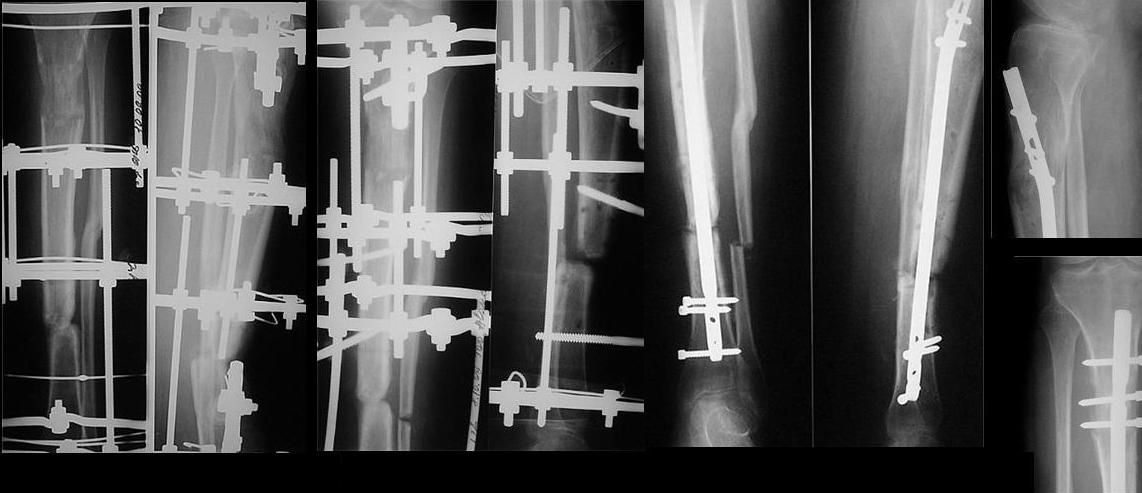

сделан первый этап операции: остеосинтез спице-стержневым аппаратом 7.11.09 г. выполнен второй этап - БИОС с рассверливанием канала, операция прошла без ожидаемых трудностей, открывать зону ложного сустава не пришлось. Прошу сделать замечания.

Рекурвация вроде осталась. Недорепонировали на этапе ЧКО.

И мы бы, наверное, динамическое блокирование сделали за счёт проксимального отломка.

И точка входа слишком низко.

И гвоздик коротковат imho.

Мы бы сделали заход через переднее межмыщелковое поле, тогда бы динамический блокирующий винт в овальном отверстии прошёл бы через нормальную кость, а не через регенерат. Ну, и стержень, соответственно, потребовался бы длиннее.